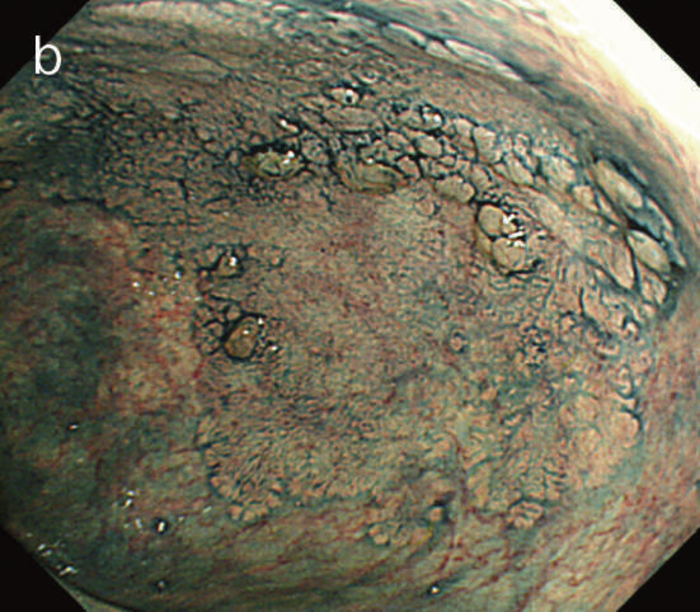

図6 UC関連LGDの内視鏡所見

- 白色光像:直腸(下部直腸)に色調変化は乏しく,微小な隆起を複数認めた。背景粘膜は寛解期にあった。

- NBI非拡大像:Brownishな領域が明らかとなった。

- 色素内視鏡像:病変辺縁が明瞭な微小な隆起を複数伴う表面平坦型病変。

- NBI拡大像:口径整でらせん状の微小血管と絨毛状の表面構造を認めた。

- pit pattern像:小型の類円形,管状pitを認めた。